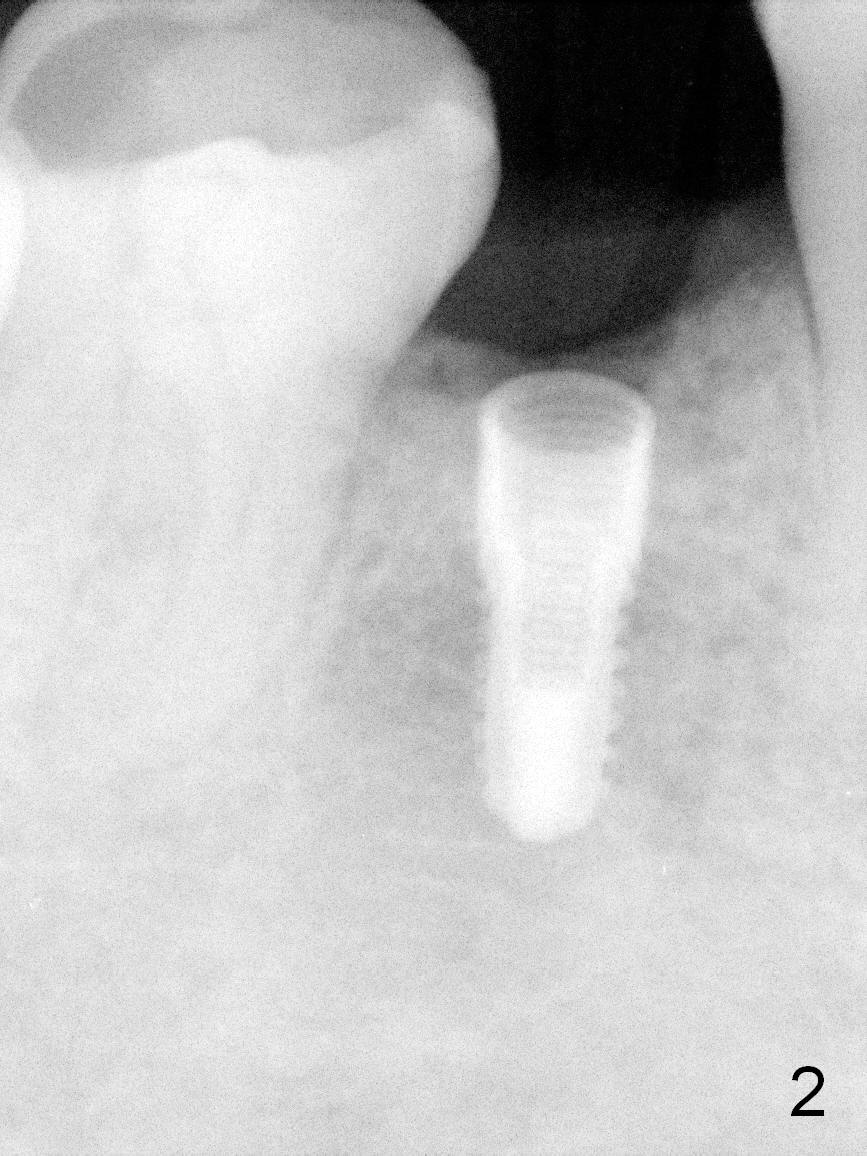

Partial edentulism with or without partial denture (especially in males) is more likely associated with implant failure than full dentition. Mr. Wang has lost several teeth (including #29, Fig.1) with secondary malocclusion, particularly supraeruption of the tooth #4. When a 3.8x10 mm submerged implant is placed with insertion torque >35 Ncm (Fig.2), an immediate provisional is selectively not placed to avoid micromovement. Instead, a healing abutment (5.2x5(3 mm) is placed immediately. For wound protection, periodontal glue and periodontal dressing are supplemented after suturing. Due to severe supraeruption of the tooth #4, the patient feels mild pain when he bites down heavily, a few hours postop. It is possible that the supraerupted tooth touches the periodontal dressing. The implant appears to be osteointegrated 4 months postop (Fig.3). A provisional is fabricated after placement of a cemented abutment (4.8x5(3) mm) to intrude the opposing tooth. There is no bone loss 2.5 years post cementation (Fig.4 CT).